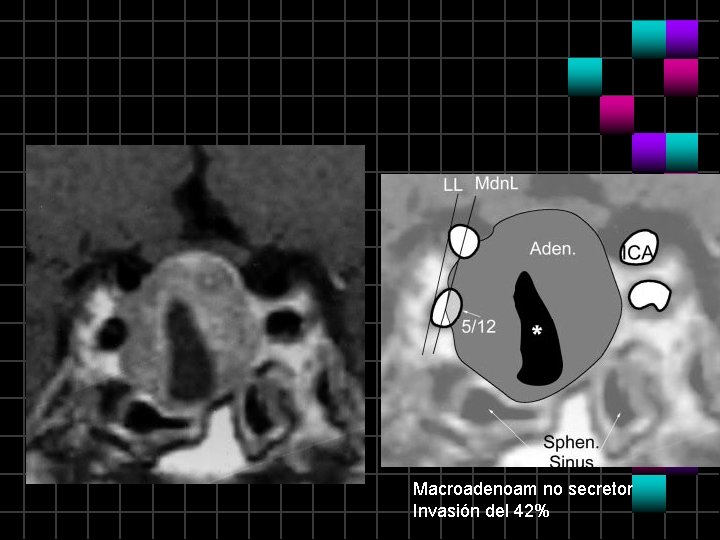

Macroadenoma no secretor

Macroadenoam no secretor Invasión del 42%